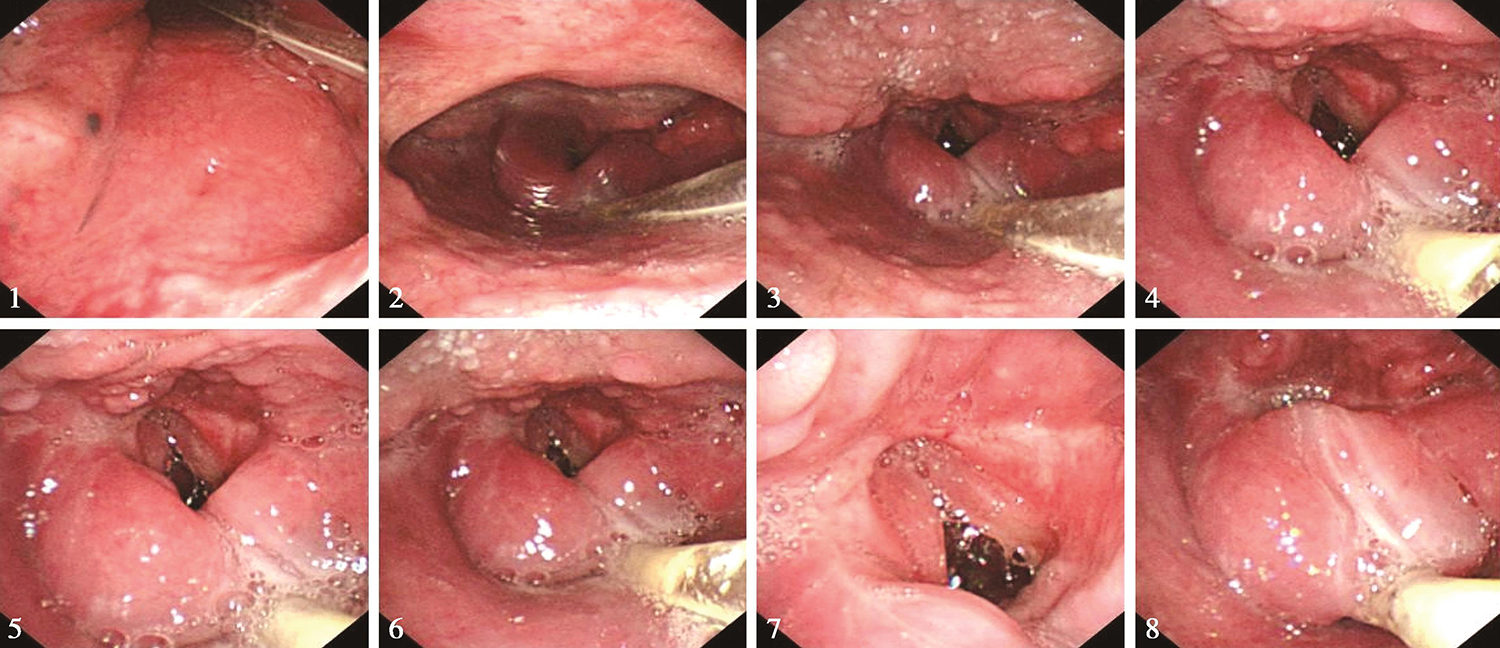

1.2015年1月5日电子鼻咽喉镜检查 检查所见:右侧鼻腔置有胃管,左侧鼻腔进镜顺利。鼻咽部表面光滑,未见明显异常。口咽双侧扁桃体未见肿大。舌根部淋巴滤泡略增生。下咽部未充分显露。喉部呈术后改变,会厌切除,会厌谷呈瘢痕样表现,双侧披裂黏膜水肿明显。双侧声带完整,黏膜充血,双侧声带活动正常,声门开放好(图4)。

图4 喉术后1个月改变,未见复发征象

内镜诊断:喉癌术后,会厌切除,残喉黏膜水肿,未见肿瘤征象。

4.2015年5月15日电子鼻咽喉镜检查 检查所见:“喉癌术后6个月”,鼻腔进镜顺利,未见明显异常。鼻咽部表面光滑,未见明显异常。口咽双侧扁桃体未见肿大。舌根部淋巴滤泡略增生。下咽部表面光滑,未见明显异常。喉部呈术后改变,会厌切除,双侧披裂对称,黏膜略水肿。双侧声带完整,活动正常,声门开放好(图6)。

图6 喉术后6个月

内镜诊断:喉癌术后,会厌切除,残喉黏膜略水肿,声门开放好,未见肿瘤复发征象。

8.2017年4月1日电子鼻咽喉镜检查 检查所见:“喉癌术后2年”,鼻腔进镜顺利。鼻咽部结构完整,黏膜光滑,未见明显异常。口咽双侧扁桃体未见肿大。舌根部淋巴滤泡增生。下咽部右侧梨状窝内侧壁和右侧环后区黏膜欠光滑(活检3块),余下咽部基本平整。喉部右侧披裂黏膜水肿,警惕侵及(图7)。左侧披裂结构基本正常。会厌切除,双侧声带基本完整,活动正常。

图7 喉术后2年,左梨状窝新生物

内镜诊断:喉癌术后,右侧梨状窝出现浅表病变(性质待病理检查),可疑为早期癌。

9.2017年4月6日右侧梨状窝活检病理 鳞状上皮原位癌,小灶不除外间质浸润。